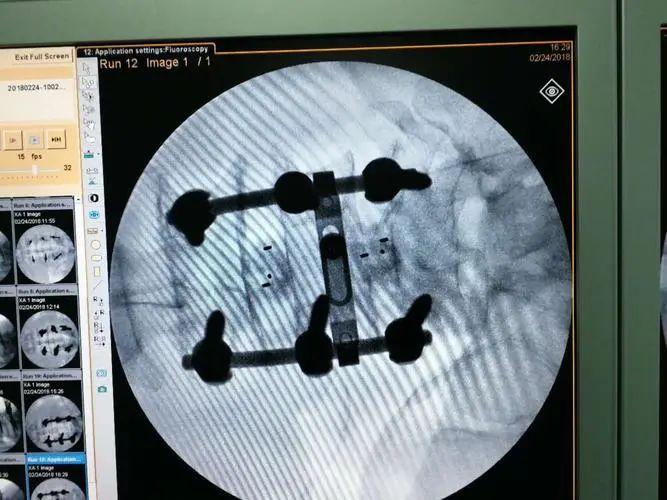

当然,支架,并不是唯一的重灾区。在高值耗材领域,仅次于支架的,当属动辄要花几万十几万的骨科耗材。后者约占在整个高值耗材市场规模的1/4

动辄受贿上千万、100套房…医疗体系的贪腐为何如此惊人?

骨科耗材的市场规模虽然略逊于支架,但是,不论是紧迫程度,还是客单价,骨科都不亚于介入。再加上与老龄化并行的日渐高发的老年退行性骨病,导致骨科耗材增速也很“喜人”。

至于骨科耗材的“油水”空间有多大,咱们还是用带量采购数据来对比一下。

前面提到,2020年10月,国内高值耗材“第一枪”打向了高值耗材第一大户——介入;2021年6月,“第二枪”就打向了高值耗材第二大户——骨科。

2022年9月27日,国家组织的骨科耗材带量采购,通过线上开标形式正式展开。第一年正式带量采购量就达到全国医疗机构总需求量的90%,价格也一步到位。

其中,用于治疗压缩性骨折的耗材,每套均价从2.7万降到1100块;胸腰椎微创手术耗材,从4万降到5600块;占脊柱手术量1/3的胸腰椎后路固定融合术耗材,从3.3万降到4500块,一些知名外资品牌价格更是从6万降到4800块

其他耗材,比如人工髋关节均价从3.5万下降至7000左右,人工膝关节均价从3.2万降至5000左右。

仅仅一套骨科耗材,均价就打下来两三万,甚至五六万。对于月收入1000块以下的五六亿人来说,这绝对是一笔巨款,直接决定了是治还是拖